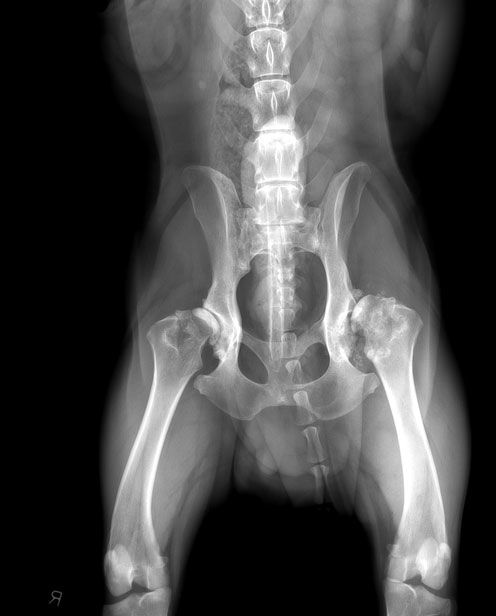

Normale Hüfte ohne Arthrose

Hier ein Bild einer normalen Hüfte ohne Arthrose eines 8 jährigen Golden Retriever Rüden. Die Hüftköpfe sind rund, glatt und sitzen tief in der Hüftpfanne.